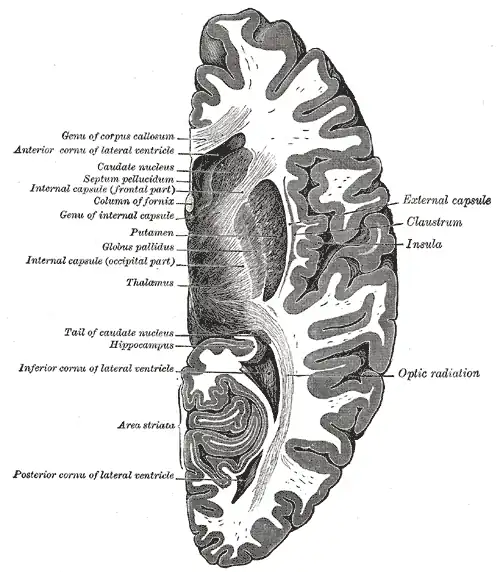

Coronal section of brain immediately in front of pons

Coronal section of brain immediately in front of pons -

Coronal section through anterior cornua of lateral ventricles

Coronal section through anterior cornua of lateral ventricles -